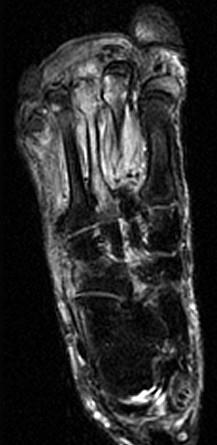

女,55岁,第3趾肿胀,结合图像,最可能的诊断是 ( )A、结核B、化脓毒性关节炎并骨髓炎C、未见异常D、骨髓炎E、化脓性关节炎

问题 女,55岁,第3趾肿胀,结合图像,最可能的诊断是 ( )

选项 A、结核 B、化脓毒性关节炎并骨髓炎 C、未见异常 D、骨髓炎 E、化脓性关节炎

答案 B